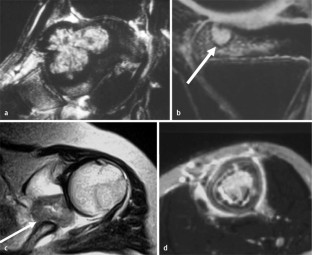

MRI morphology of bone tumors and tumor-like lesions

Für das Staging und die Charakterisierung von Knochentumoren und tumorähnlichen Läsionen ist in der Magnetresonanztomographie (MRT) der Einsatz von Spinechosequenzen erforderlich. Die MRT hat nur einen geringen Stellenwert in der Bestimmung der Dignität. Obwohl viele Knochentumoren und tumorähnliche Läsionen eine vergleichbare Morphologie in dieser bildgebenden Modalität aufweisen, können einige Tumorentitäten mittels MRT recht zuverlässig diagnostiziert werden. Hierzu zählen Knorpeltumoren, die solitäre und aneurysmatische Knochenzyste, der Riesenzelltumor, fetthaltige Läsionen und bis zu einem gewissen Grad auch das Osteoidosteom und das Osteoblastom. Es werden praktische Tipps gegeben, wann bei Tumorverdacht die MRT eingesetzt werden sollte, wie bei einem zufällig bei einer MRT gefundenen Tumor die Untersuchung modifiziert werden sollte und welcher Tumor vorliegen könnte.

Spin-echo sequences are mandatory at MRI for staging and characterization of bone tumors and tumor-like lesions. MRI is of minor value in the estimation of the malignant potential of an osseous lesion. Although many bone tumors and tumor-like lesions present similar morphology at MRI, some entities can be diagnosed with good reliability. These include chondrogenic tumors, solitary and aneurysmal bone cysts, giant cell tumors, lesions containing fatty tissue and, to a certain extent, osteoid-osteomas and osteoblastomas. Practical advice is given regarding when to perform a MRI study in cases of tumor suspicion. Further advices are given for cases a tumor is found incidentally at a MRI study, how to modify the study and which kind of tumor may be present.